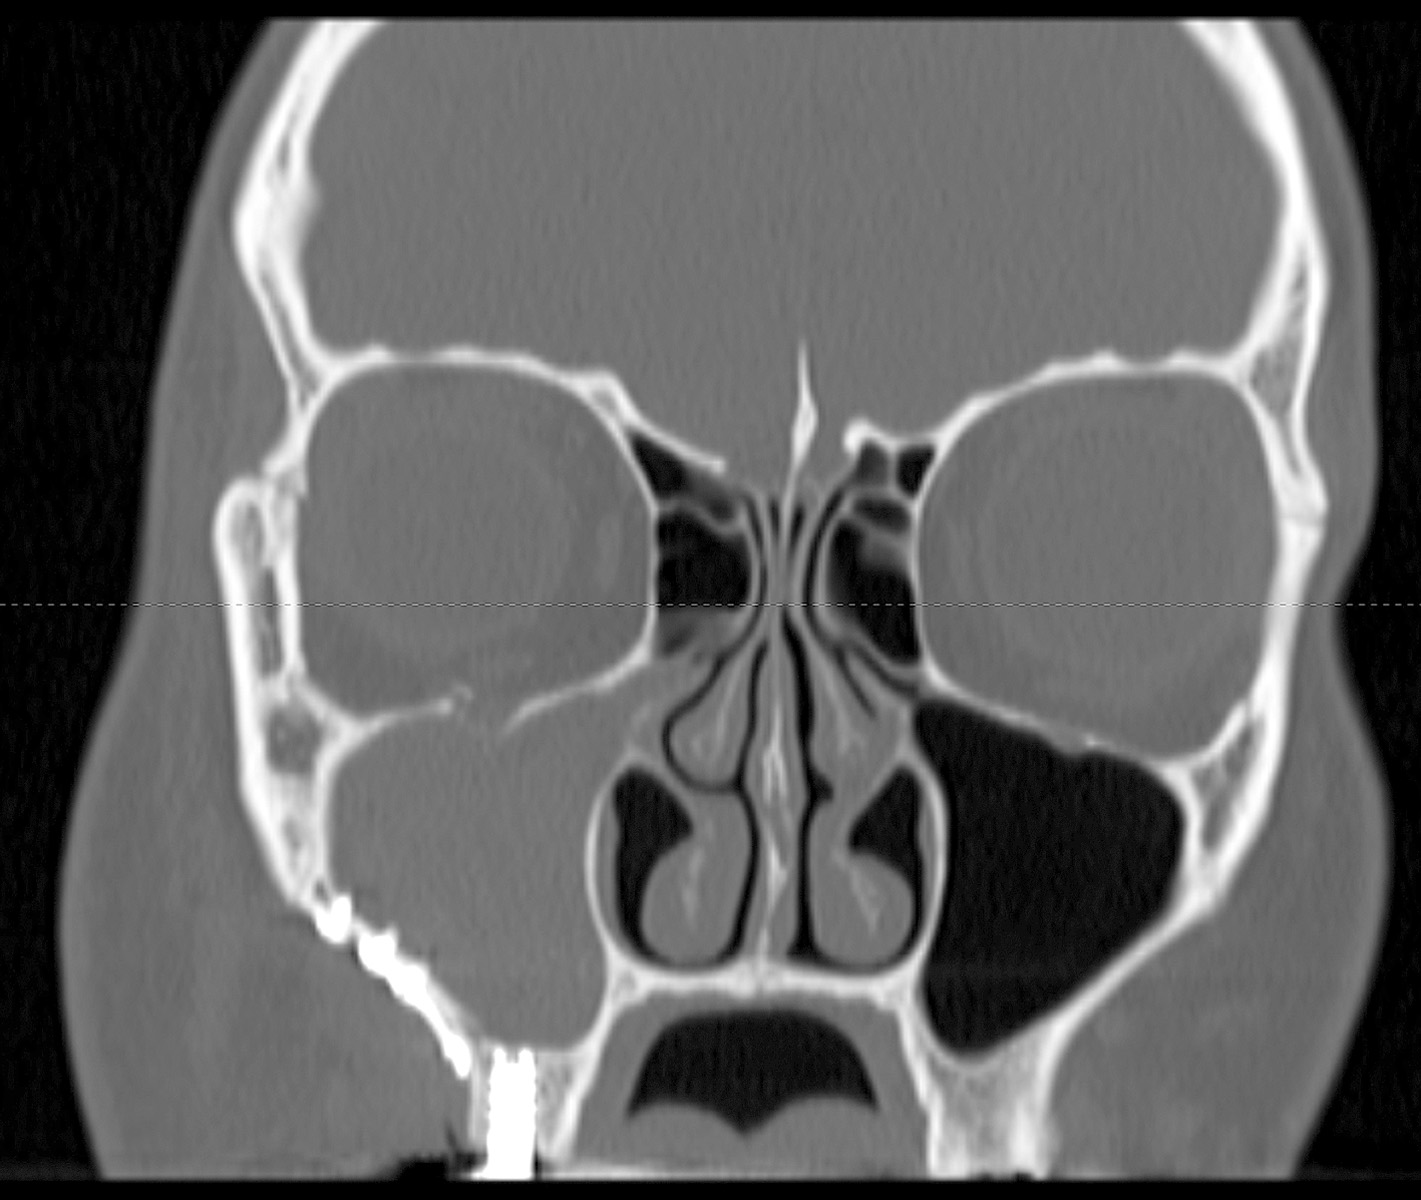

КТ-снимки хронического этмоидита: подробная визуализация

Раздел: Фотодневник открытий